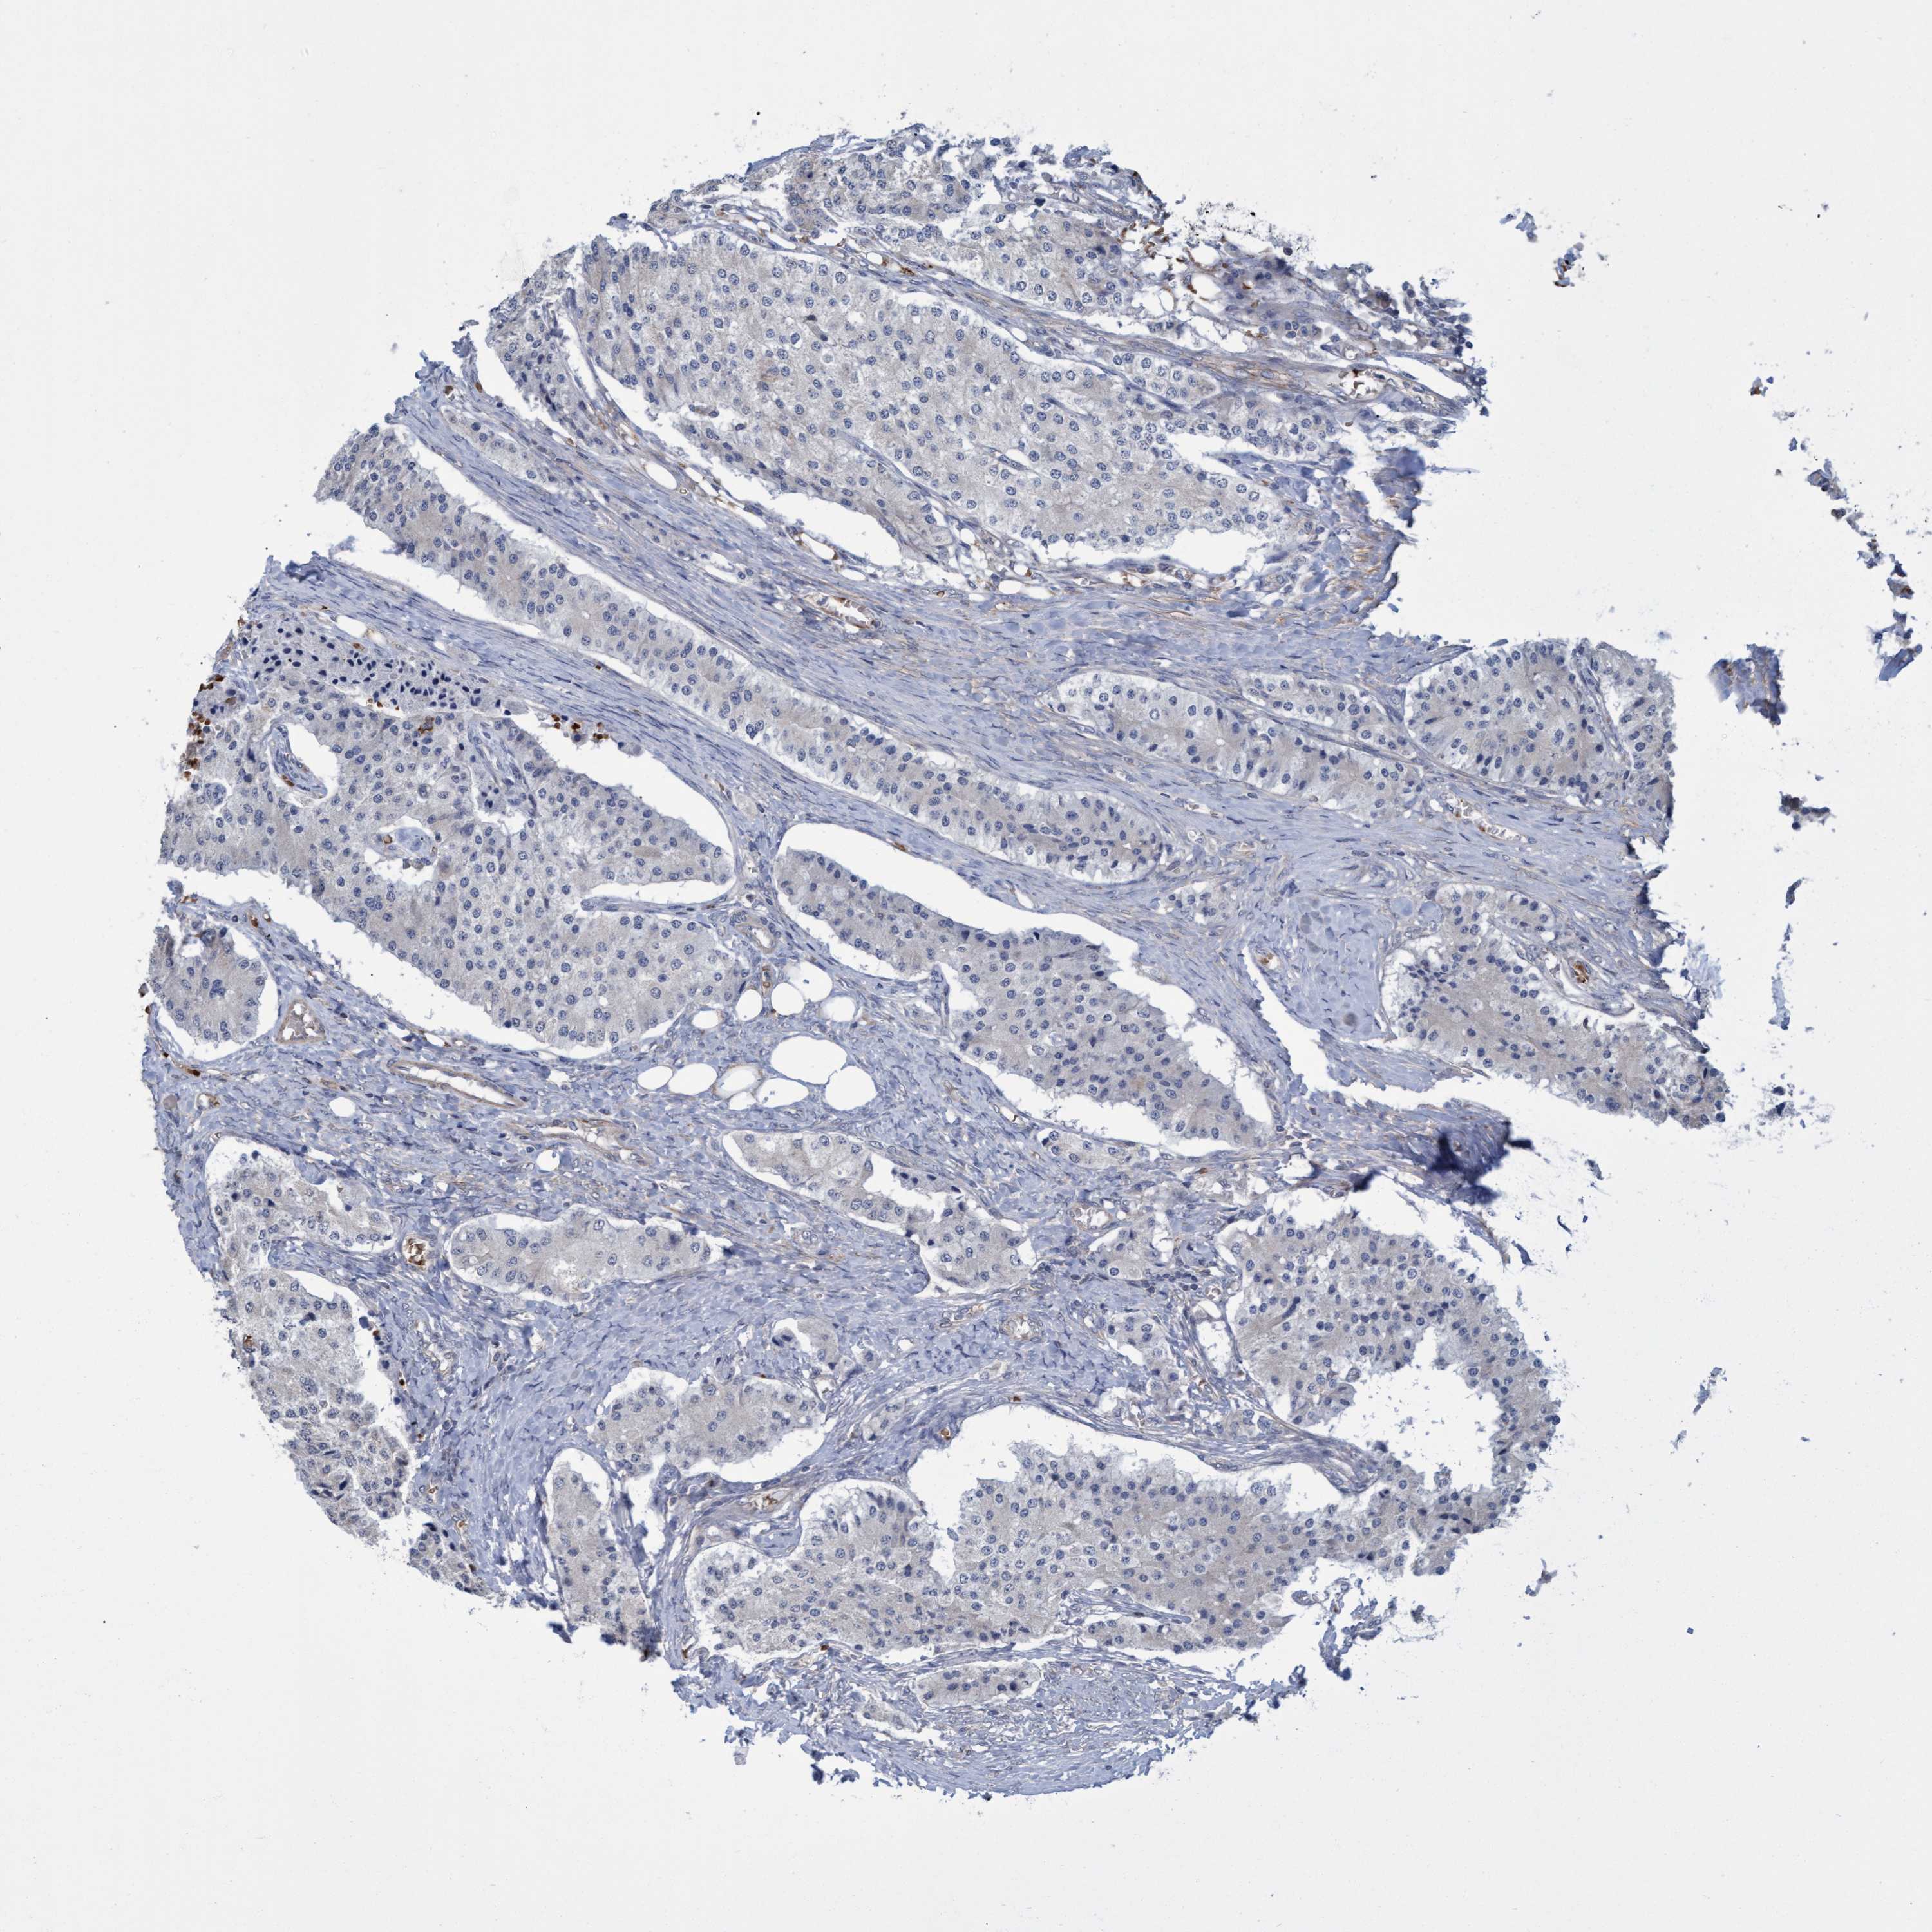

NAA15